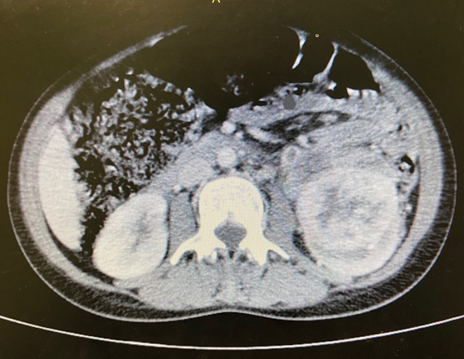

The abdominal image showed enlargement of the left kidney with a solid, expansive lesion that exhibited irregular contours and heterogeneous contrast enhancement, measuring 6.4cm along its longest axis, with involvement of the ureter and gonadal vein. In the pelvis, an extensive, expansive formation was identified in the bladder with a vegetative and infiltrative aspect, with uptake similar to that associated with renal injury and signs of invasion of the abdominal wall and pubic bones (Figures 1,2).

Figure 1 Computed tomography image of a massive solid lesion in the left kidney.

Figure 2 Computed tomography image of an infiltrative mass in the bladder.